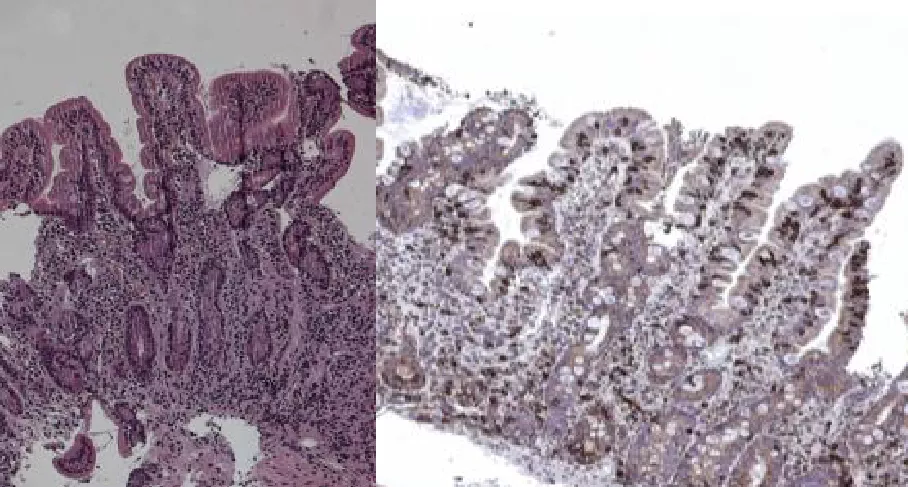

Стадия Marsh 1 (инфильтративная)

Характеристика: нормальная высота ворсинок, неглубокие крипты, соотношение ворсинка/крипта 3-4 к 1, количество МЭЛ увеличено (более 25% от количества энтероцитов). Подсчет числа МЭЛ упрощается при проведении иммуногистохимического исследования на CD3+ лимфоциты (см. на рисунке – CD3+МЭЛ прокрашены коричневым цветом) |